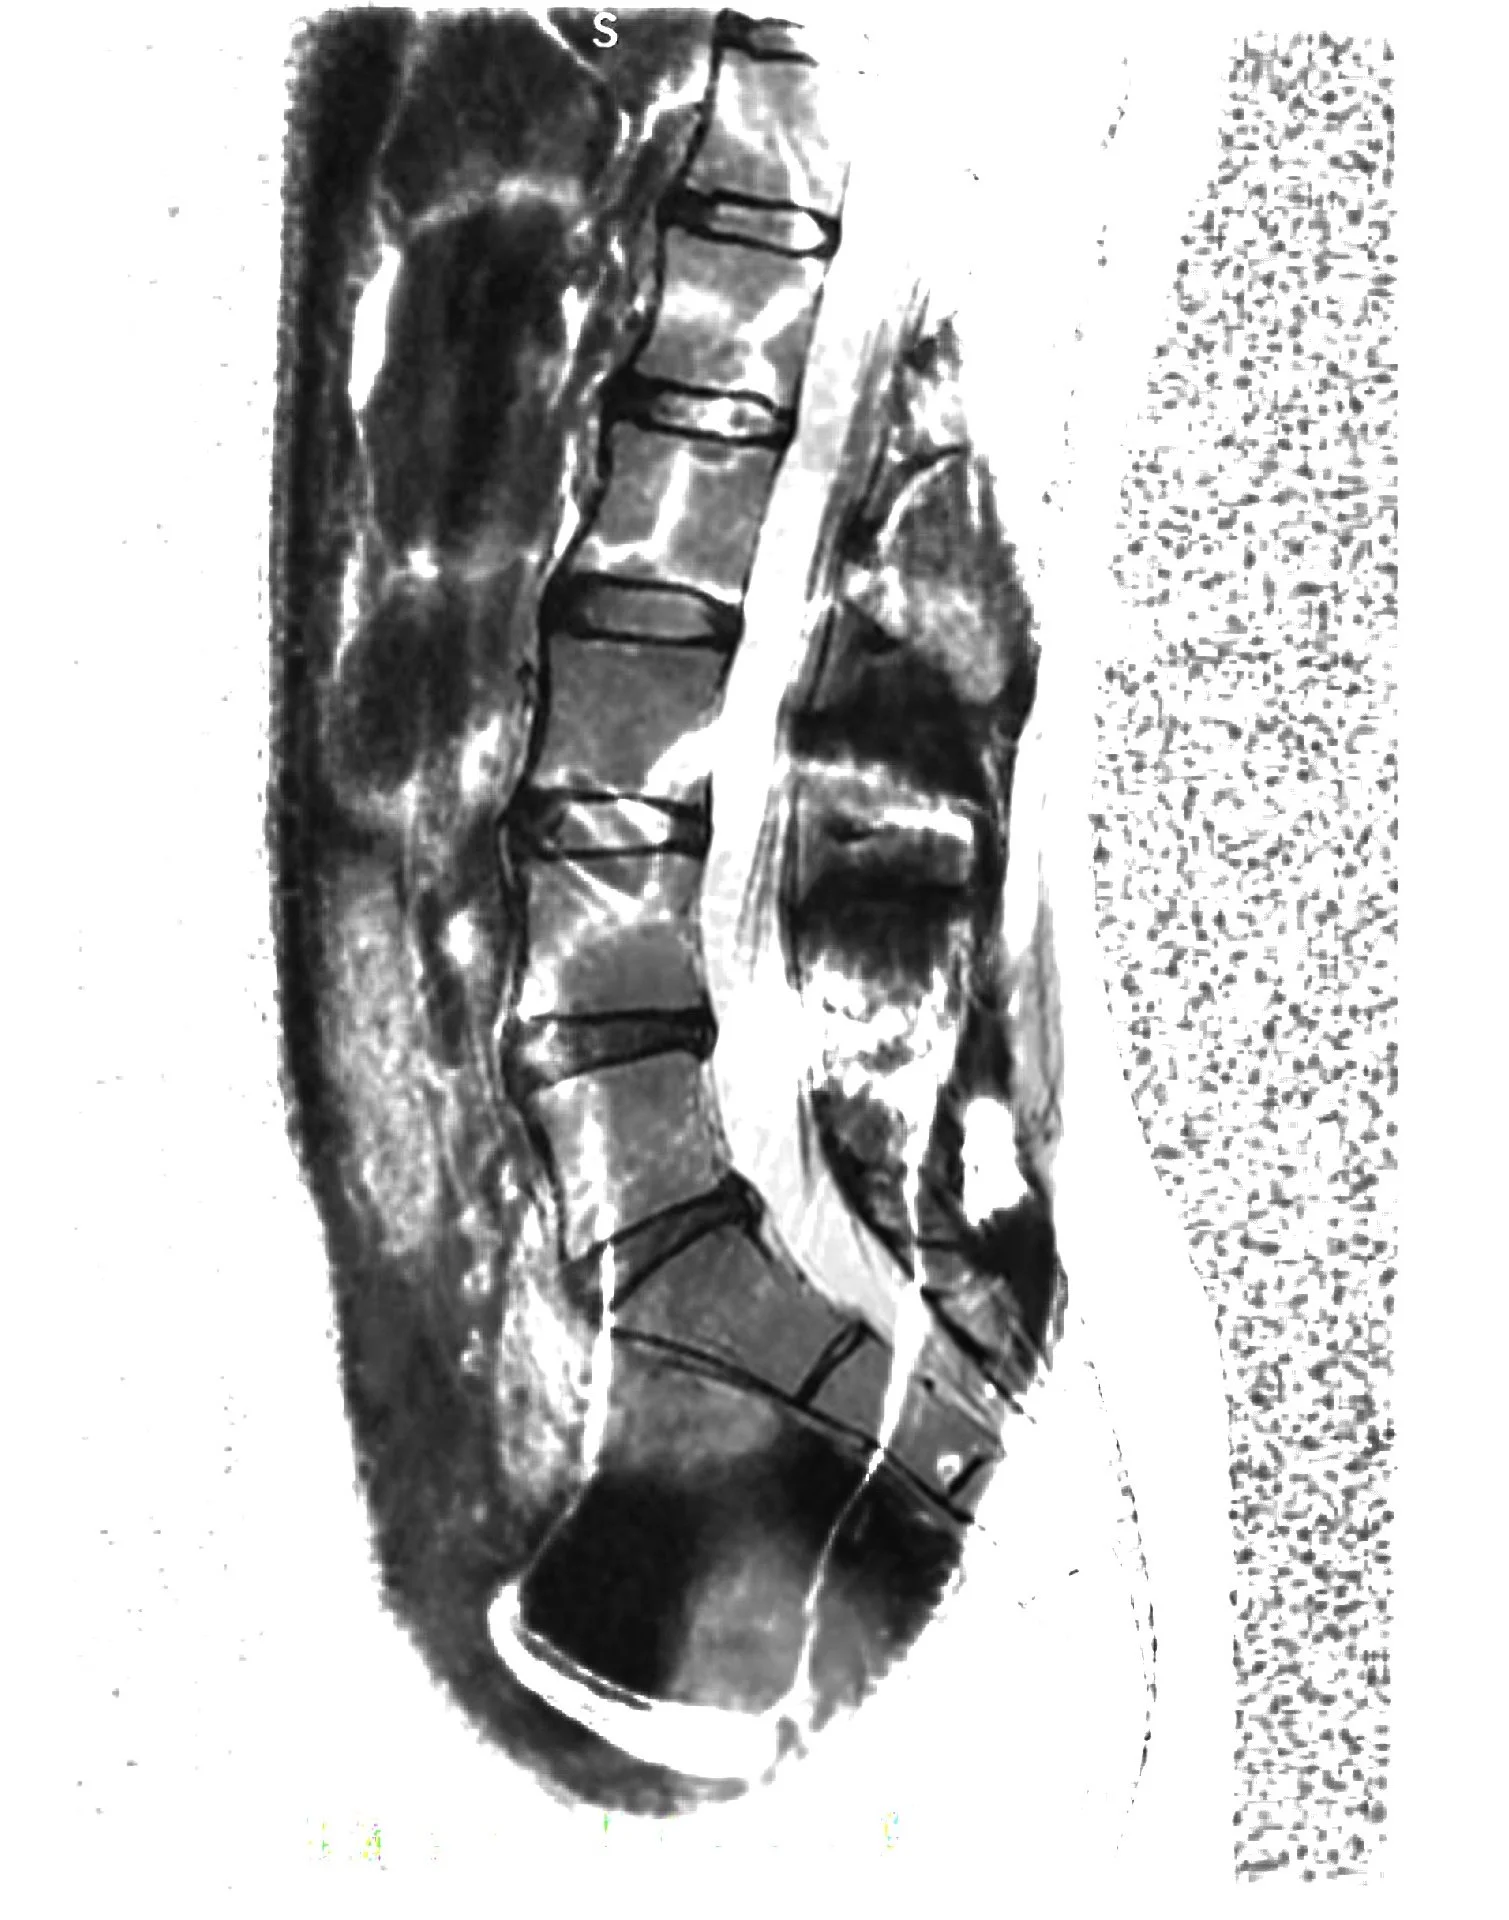

As my usual ways of creating became untenable, I experimented with different creative processes that were in line with my declining and changing function: painting with my feet when my neck injury affected my hand function, audio-transcribing prose, drawing while lying down or walking, pacing with clay and imprinting it into trees outside, overlaying medical images on my phone from my bed, and working at odd hours, including the middle of the night.